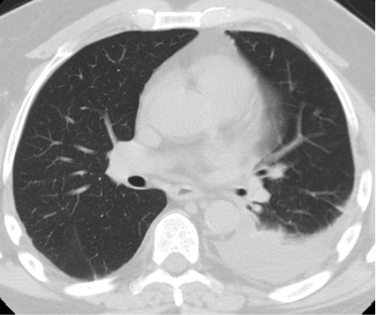

Case Presentation: A 63-year-old male presented to our institution with progressive dyspnea and associated hemoptysis of several days duration. He was a former cigarette smoker, having smoked approximately 1 pack per day for 45 years, who had recently transitioned to using electronic cigarettes, or “vaping,” 3 months prior. With regards to his vaping, he reported using both cannabidiol (CBD) and flavored solutions in attempts to abstain for further cigarette use. He had no recent respiratory illness and no documented history of malignancy, pulmonary embolism, COPD or other lung disorders. On admission, he was afebrile, oxygenating well and with stable hemodynamics. There was no leukocytosis and initial infectious work up was negative. Chest radiograph revealed a new left-sided pleural effusion. Subsequent CT angiogram of the chest and pulmonary arteries was without pulmonary embolism but confirmed the presence of the left-sided effusion. He underwent thoracentesis with the removal of 700 mL of serous fluid. Pleural studies were consistent with an exudative effusion by Light’s criteria. Cytology was negative for malignant cells. Repeat CT of the chest revealed an 8 mm pleural-based thickening on the right but no findings on the left. He was evaluated by pulmonology who recommended repeat CT imaging in 4 weeks and discontinuation of further electronic cigarette use. The patient felt significantly improved and repeat CT of the chest following abstinence from further vaping was without re-accumulation of the left-sided effusion. The pleural thickening noted on the right side appeared stable with no progression on repeat imaging.